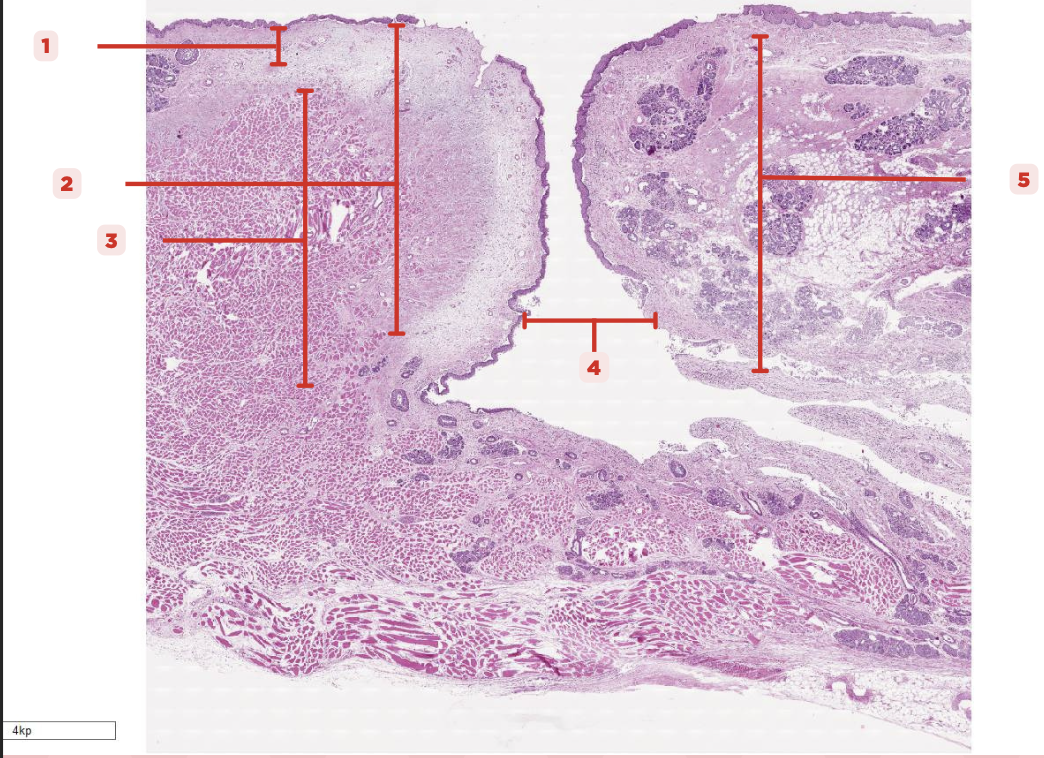

Nasal Cavity

What are the spaces found immediately lateral to #2?

Nasal Turbinates (conchae)

Identify the structure labeled as 1.

Nasal septum

Identify the structure labeled as 2.

Nasal cavity

Identify the structure labeled as 3.

Hard palate

Identify the structure labeled as 4.

Mucosal Associated Lymphoid Tissue (MALT)

What time of lymphocyte is numerous in the nasal cavity?

Loose Connective Tissue

What type of cells make up #1?

Lamina Propria

Identify the structure labeled as 1.

Hyaline Cartilage

Identify the structure labeled as 2.

Respiratory Epithelium

Identify the structure labeled as 3.

Nasal Cavity

Identify the structure labeled as 4.

Basal Cells

Identify the structure labeled as 5.

Goblet Cells

Identify the structure labeled as 6.

Ciliated Columnar Cells

Identify the structure labeled as 7.